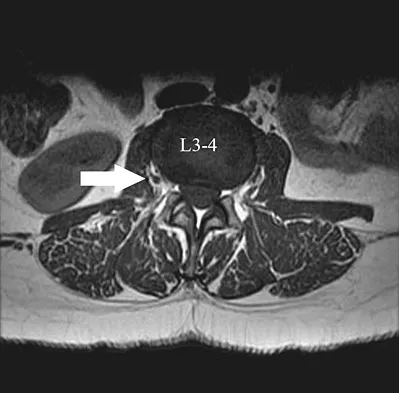

A 46-year-old woman who was involved in a motor vehicle accident reports a 4-month history of right-sided lower back pain and pain radiating into the right thigh. The patient underwent an extensive 3-month course of physical therapy and now is dependent on narcotic medication for pain control. Epidural injection therapy has failed to improve her symptoms. Examination is significant for weakness of hip flexion in the seated position and for decreased sensation to light touch in the medial anterior thigh region. Straight leg raise is negative, but the femoral stretch test reproduces anterior thigh pain. A CT myelogram image, at L3-L4, is shown in Figure 3. What is the most appropriate management at this time?